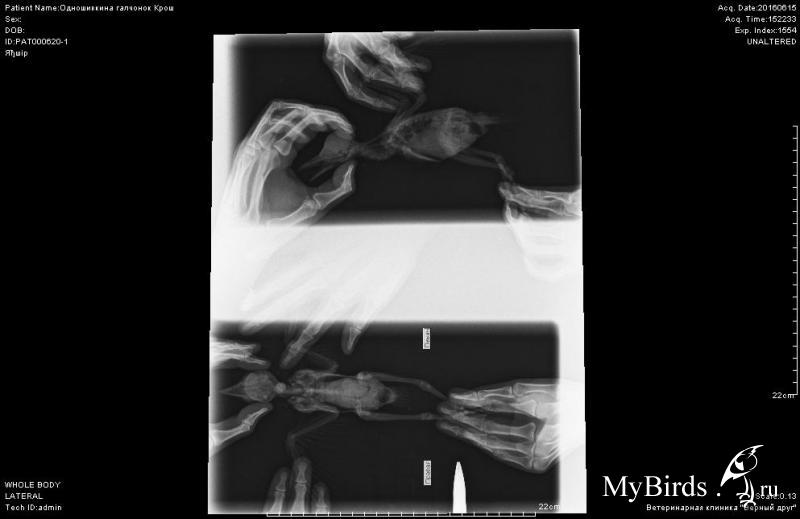

В увеличенные снимки вошло только туловище. Мне кажется, кишечник воспалён?

Судя по рентгену, у птенца был воспален кишечник, Зося предположила, что у него глисты, но мы не успели помочь.